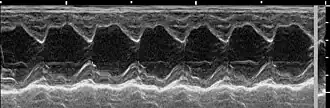

Die häufigsten Anzeichen einer verschlechterten Herzfähigkeit sind: abnehmende Leistungsfähigkeit, Husten, nächtliche Unruhe und Dyspnoe. In der Auskultation sind in den meisten Fällen holosystolische Herzgeräusche konstanter Intensität in verschiedensten Lautstärken (Grad 1 bis Grad 6) wahrnehmbar. Das lauteste Geräusch (Punctum maximum) der Mitralklappe liegt beim Hund im 5. Interkostalraum auf Höhe der Herzspitze. Im Röntgenbild ist häufig ein vergrößertes Herz feststellbar. Der linke Vorhof kann hierbei in Form eines Dreieckes („Mitralisdreieck“) nach kaudo-dorsal hervortreten. Die häufig feststellbare Abwinkelung zwischen Luftröhre und Wirbelsäule kann einem parallelen Verlauf gewichen sein, teilweise kann der Vorhof sogar die Luftröhre komprimieren und infolge der hierdurch verursachten mechanischen Reizung die Hustensymptome noch verstärken. In fortgeschrittenen Fällen liegt ein Lungenödem vor. Das Elektrokardiogramm ist häufig wenig spezifisch, teils sind Hinweise auf einen vergrößerten Vorhof (verlängerte P-Welle, über 0,04 Sekunden) oder eine vergrößerte Hauptkammer (QRS-Komplex länger als 0,06 Sekunden) erkennbar. Daneben kann es zur Ausbildung von Vorhof- oder Kammerextrasystolen kommen, in einigen Fällen wird ein Vorhofflimmern beobachtet. Dieses Symptom ist bei Hunden mit funktionellen Mitralinsuffizienzen aufgrund einer dilatativen Kardiomyopathie häufig. Echokardiografisch ist eine Mitralklappeninsuffizienz anhand einer Doppleruntersuchung leicht erkennbar. Daneben treten als Effekte auf: erweiterte Hauptkammer aufgrund der Volumenüberlastung, häufig Hyperkontraktilität aufgrund von Kompensationsmechanismen, deutlich vergrößerter Vorhof.